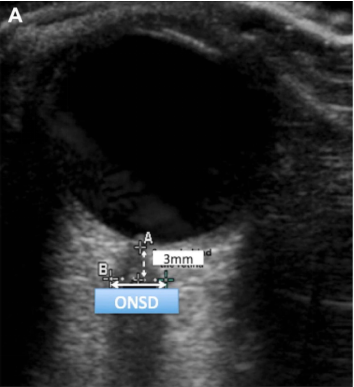

(4)神经系统并发症:神经系统并发症在VV-ECMO和VA-ECMO中都非常常见。颅脑超声无创,可估算颅内压及脑灌注压,实时监测,适合于使用抗凝剂的ECMO患者。经颅多普勒(TCD)和视神经鞘测量,能够协助识别脑梗死,脑出血等,以及脑评估死亡。经颅多普勒甚至可以进行脑死亡的评估,例如振荡波、钉子波、波形消失都提示脑死亡的可能(图5)。对于视神经鞘的监测,在视网膜后方3 mm可以测量视神经鞘的直径(图6),视神经鞘直径>5 mm,提示颅内高压。

图片

图6  视神经鞘的监测